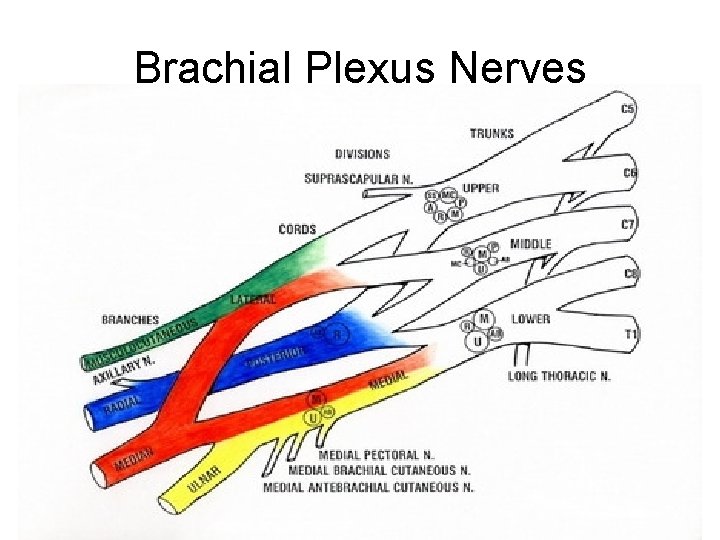

Brachial plexus anatomy • The brachial plexus extends from C 5 to T 1; (C 5, C 6, C 7, C 8 and T 1). • It innervates the shoulder and arm. • The brachial plexus begins as spinal nerve roots and continues to the terminal branches that supply the upper extremity. • Specifically, the anatomy progresses from roots to trunks, trunks to divisions, divisions to cords (lateral, medial and posterior cords) and finally to terminal nerve branches

Brachial Plexus Nerves